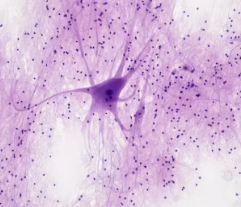

대상포진 후 신경통은 수두-대상포진 바이러스가 신경을 손상시키면서 발생합니다. 바이러스가 활성화될 때 신경절과 주변 신경 섬유에 염증을 일으키고, 이 손상이 회복되지 않고 남아 통증을 지속시키는 것입니다.

손상된 신경은 통증 신호를 비정상적으로 뇌에 전달하여 피부 발진이 사라진 후에도 통증을 느끼게 만듭니다.